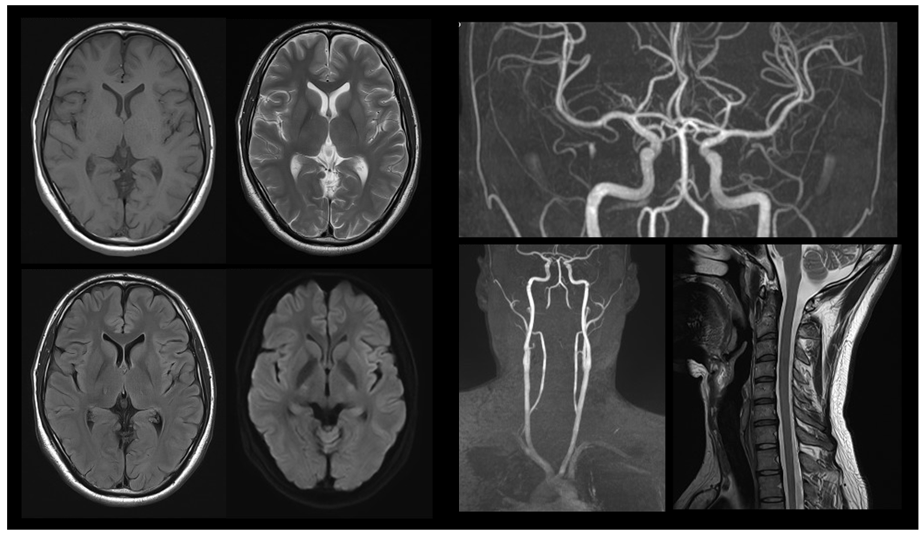

磁力を使用し、体のあらゆる断面を画像化

MRI検査は強い磁力を使用し、体のさまざまな断面を画像化できる検査です。CT検査と異なりエックス線を使用しません。エックス線による被ばくはありませんが強い磁力を使用するため、金属類(磁性体:磁力の影響を強く受ける金属)には注意が必要です。

MRI検査の撮影部位は全身が対象で、造影剤を使用しない「単純検査」と造影剤を使用する「造影検査」があります。

MRIは強力な磁力と電磁波を使用し、人体のあらゆる部位を画像化します。CT検査と異なり、骨や空気の多い部位にも適した検査です。また、CTよりも臓器や筋肉などを詳細に画像化することができ、造影剤を使用せずに血管を画像化する事も可能です。

新規機器を購入いたしました

2024年4月に3.0テスラMRI装置を導入しました。以前のMRIと比べ、画質の向上・検査時間の短縮が可能になりました。装置のトンネル部分も以前より広くなり、圧迫感が軽減されるような構造となっています。また、検査室内は開放的な空間になることを意識し、天井と壁の一部に空模様のパネルを配置しました。患者さまに、より安心して検査を受けていただける内装になっています。